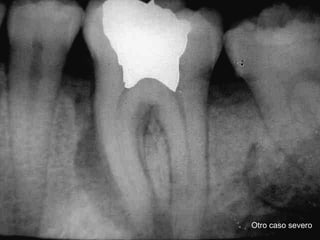

Parodontopatía

Encia sana

Inserción Gingivodentaria sana

Ruptura del anillo de

Kolhiker

Primer absceso gingivodentario sin compromiso

Oseo aparente.

Qué es

Profundización relativamente asintomática de la

Placa bacteriana

Absceso parodontal severo, con sintomatología franca

Destrucción del parodonto

Otro caso severo